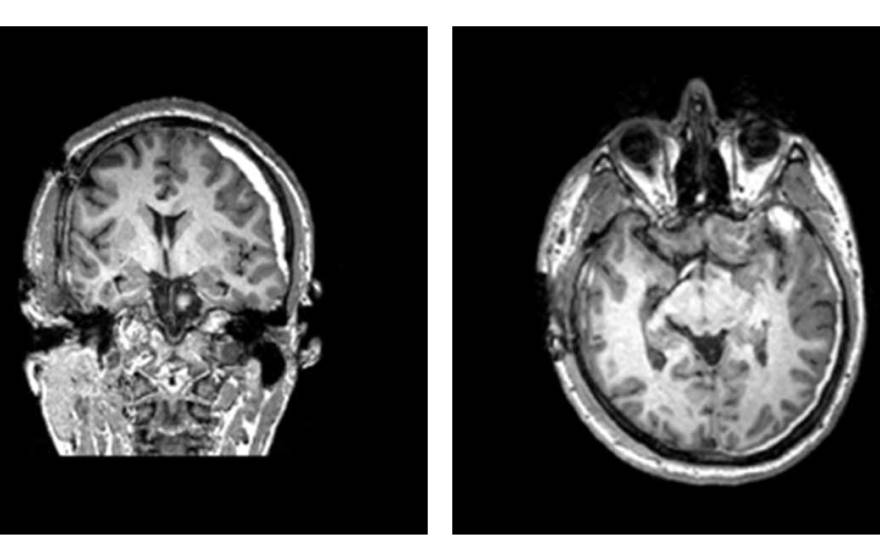

UC San Francisco |

I’m a stroke doctor. Here’s how I reduce my own risk

Poverty, stress, limited access to healthy foods and certain medical conditions up the ante – especially in women. For this UC San Francisco neurologist, it’s personal.